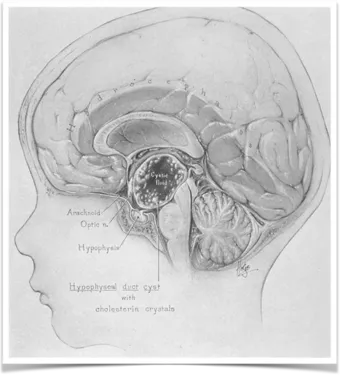

早在20世纪90年代,神经外科学奠基人Harvey Cushing即将颅咽管瘤定性为最可怕的颅内肿瘤。尽管其病理分级仅为WHO I级,发病率亦低于垂体腺瘤,然而病理分级的低度恶性并不等同于临床处置的低...

作为小儿神经外科领域的国际大咖,INC旗下世界神经外科顾问团成员James T.Rutka教授早在2008年的《Initial Management of Childhood Brain Tumors:Neurosurgical Considerations》论文中综述了颅咽管瘤的治疗及预后进...